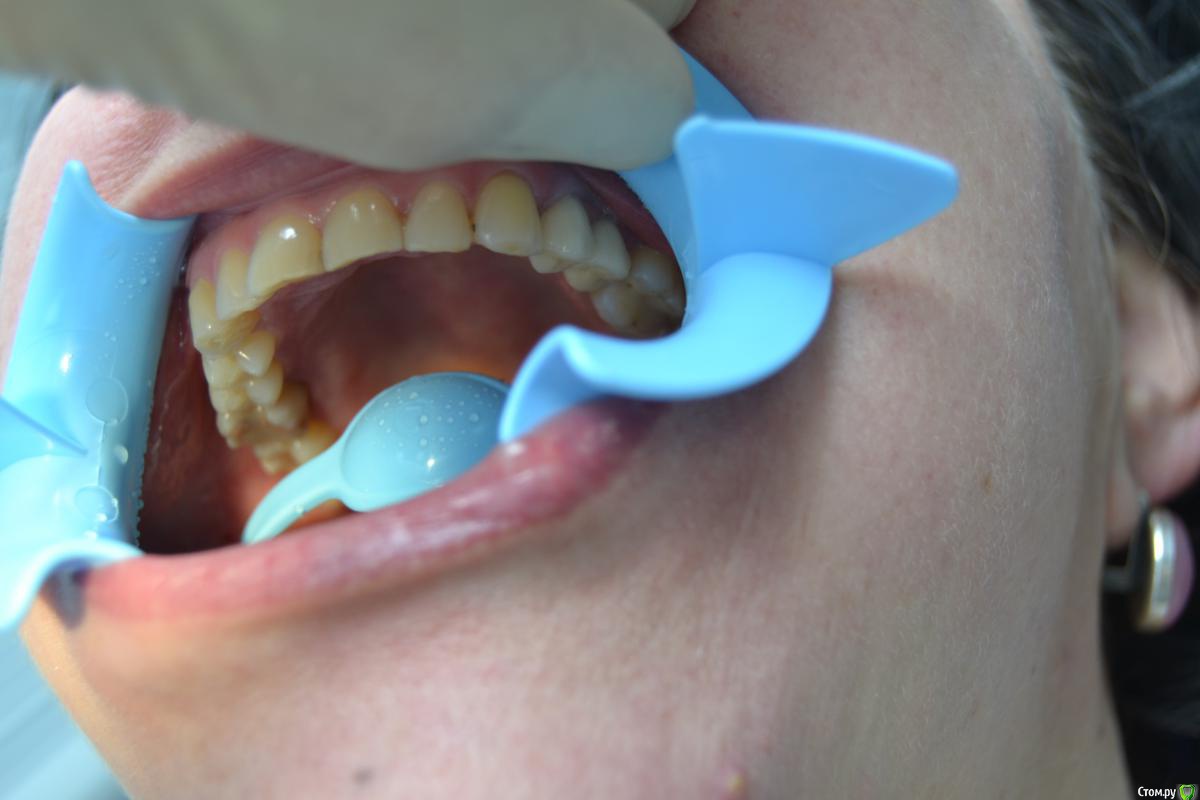

dantist_movani Опубликовано 5 февраля, 2017 Поделиться Опубликовано 5 февраля, 2017 (изменено) Имплантаты niko leader. 3.6*10 мм и 3.6*8 мм в позиции 2.4 и 2.5.Тот случай когда пациент уверен в тебе больше, чем ты сам. Руки тряслись, делал без хирургического шаблона. Первый имплантат, в области 2.4 не заглубил, стабильности имплантата в области 2.5 не было, прокручивался. После операции сделали снимок сразу расстроился, то что криво закрутил, расстояние между имплантатами 1.3 мм в области заглушек. Через 10 дней сняли швы, все хорошо...Через месяца два в области 2.5 над заглушкой свищ с отделяемым. Сделал анестезию, кюретаж над заглушкой, назначил антибактериальную и противовоспалительную, все нормализовалось. Через 5 месяцев ФДМ, все стабильно и через 3 недели коронки у ортопеда. Жуём уже 8 месяцев, Слава Богу!!! Изменено 5 февраля, 2017 пользователем dantist_movani Ссылка на комментарий

Rasim-AZ Опубликовано 5 февраля, 2017 Поделиться Опубликовано 5 февраля, 2017 Жесткая стираемость у пац Ссылка на комментарий